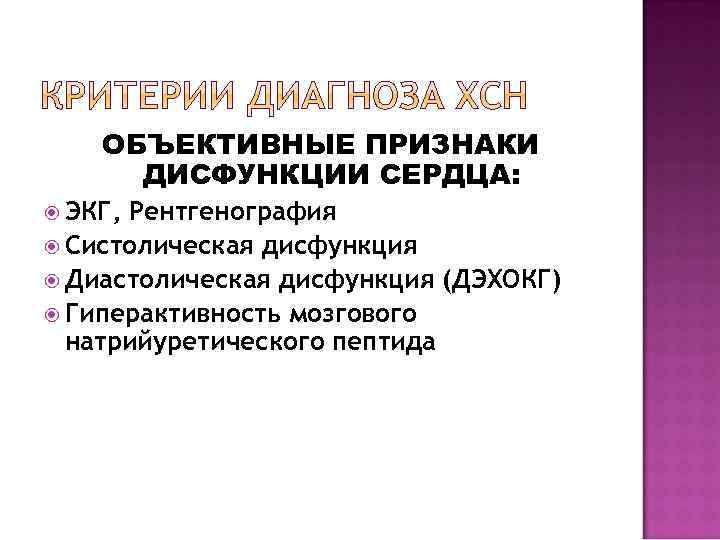

ОБЪЕКТИВНЫЕ ПРИЗНАКИ ДИСФУНКЦИИ СЕРДЦА: ЭКГ, Рентгенография Систолическая дисфункция Диастолическая дисфункция (ДЭХОКГ) Гиперактивность мозгового натрийуретического пептида

ОБЪЕКТИВНЫЕ ПРИЗНАКИ ДИСФУНКЦИИ СЕРДЦА: ЭКГ, Рентгенография Систолическая дисфункция Диастолическая дисфункция (ДЭХОКГ) Гиперактивность мозгового натрийуретического пептида